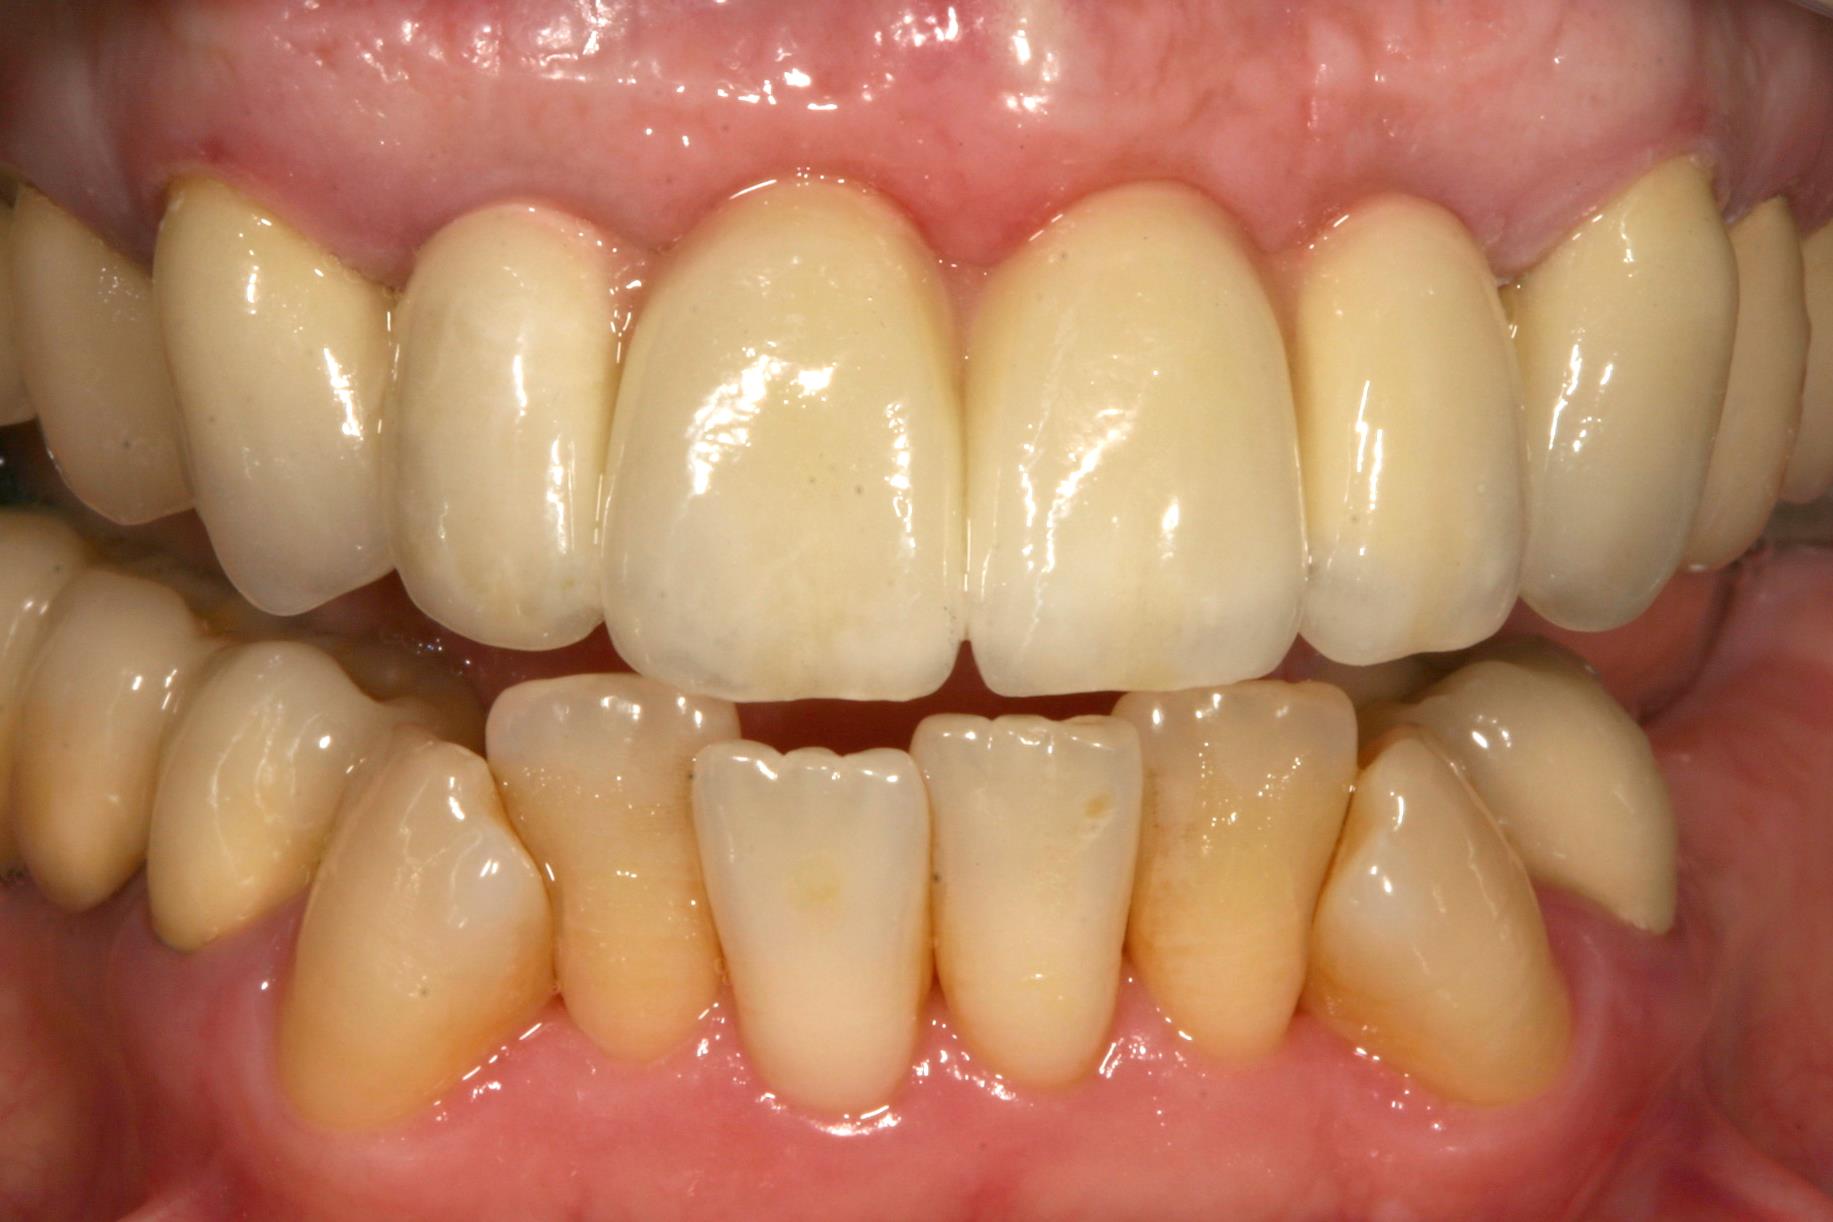

Wenn mehrere Zähne im Frontzahnbereich fehlen, kann man die Lücke durch eine Brücke schließen. Meistens ist dann auch schon der Kieferkamm zurückgeschwunden. Dadurch wirken die Brückenglieder länger. Auch die Zahnfleischpapille fehlt. Hier haben wir sie mit rosa Keramik nachgebildet, um „dunkle Löcher“ zwischen den Zähnen zu vermeiden und die Zähne nicht unnatürlich breit und lang erscheinen zu lassen.